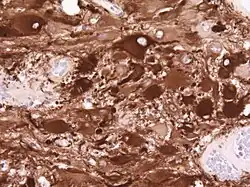

No tecido tumoral, em geral, a maior proporção de realce pelo contraste se deve à barreira hemato-tumor particular que permite a passagem de iodo (TC) e gadolínio (RM) para o espaço intersticial extravascular intratumoral. Isso aumenta o sinal (densidade ou intensidade) do tumor. No entanto, deve-se ter cuidado para garantir que o realce do contraste não diferencie definitivamente a neoplasia do edema periferida. De fato, o achado anátomo-patológico no tecido tumoral de glioma infiltrante maligno, como no glioblastoma e no astrocitoma anaplásico, também mostra além do edema vasogênico causado pela destruição da barreira hematoencefálica pelo tumor. Esta última condição clínica é pouco detectável pelo diagnóstico por imagem.

Vários sistemas de categorias foram propostos na literatura ao longo do tempo para classificar a malignidade dos astrocitomas. Desde 1993, o sistema de classificação de quatro níveis proposto pela Organização Mundial da Saúde (WHO) tem sido o mais utilizado e aplicado. Baseia-se em quatro características histológicas: aumento da densidade celular, mitose, proliferação endotelial e necrose. Posteriormente, astrocitomas de grau I, como astrocitomas pilocíticos, são tipicamente de histologia benigna. Astrocitomas II. Os graus (difusos) mostram o aumento da densidade celular como única característica histológica e são neoplasias com menor grau de infiltração. Astrocitomas III mostram uma mitose significativa. grau (anaplástico). E proliferação endotelial ou necrose são vistas em astrocitomas IV. graus, os chamados glioblastomas.

Os tumores de células gliais mais comuns e malignos são os glioblastomas. Consistem em uma massa heterogênea de células de astrocitoma pouco diferenciadas principalmente em adultos. Geralmente ocorrem nos hemisférios cerebrais, mais raramente no tronco cerebral ou na medula espinhal. Exceto em casos muito raros, como todos os tumores cerebrais, eles não se estendem além das estruturas do sistema nervoso central.

O glioblastoma pode surgir de uma forma difusa (II. grau) ou um astrocitoma anaplásico (III. grau) se desenvolvem. Neste último caso, é chamado de secundário. No entanto, quando ocorre sem antecedentes ou evidência de malignidade prévia, é referido como primário. Os glioblastomas são tratados com cirurgia, radioterapia e quimioterapia. Eles são difíceis de curar e há poucos casos que sobrevivem além de três anos.